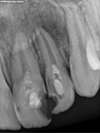

Traitement au laser seul

Le kyste a disparu et l'os est revenu !